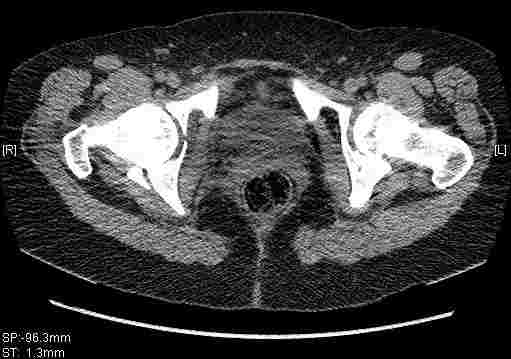

Остальные срезы.